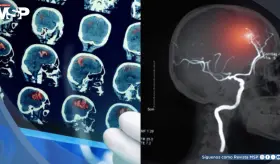

El ACV es una emergencia médica causada por la interrupción del flujo sanguíneo al cerebro, ya sea por una obstrucción (isquémico) o por la ruptura de un vaso (hemorrágico).

La detección inmediata del ACV es decisiva: cada minuto sin atención implica la pérdida de millones de neuronas, por lo que reconocer síntomas y activar el 911 marca la diferencia entre recuperación y discapacidad permanente.

Determinar si un paciente con stroke es candidato a trombolisis o trombectomía requiere precisión clínica y un manejo coordinado.

La investigación mostró particularidades en la distribución de tipos de ACV: 50.7% isquémicos frente a 41.9% hemorrágicos.